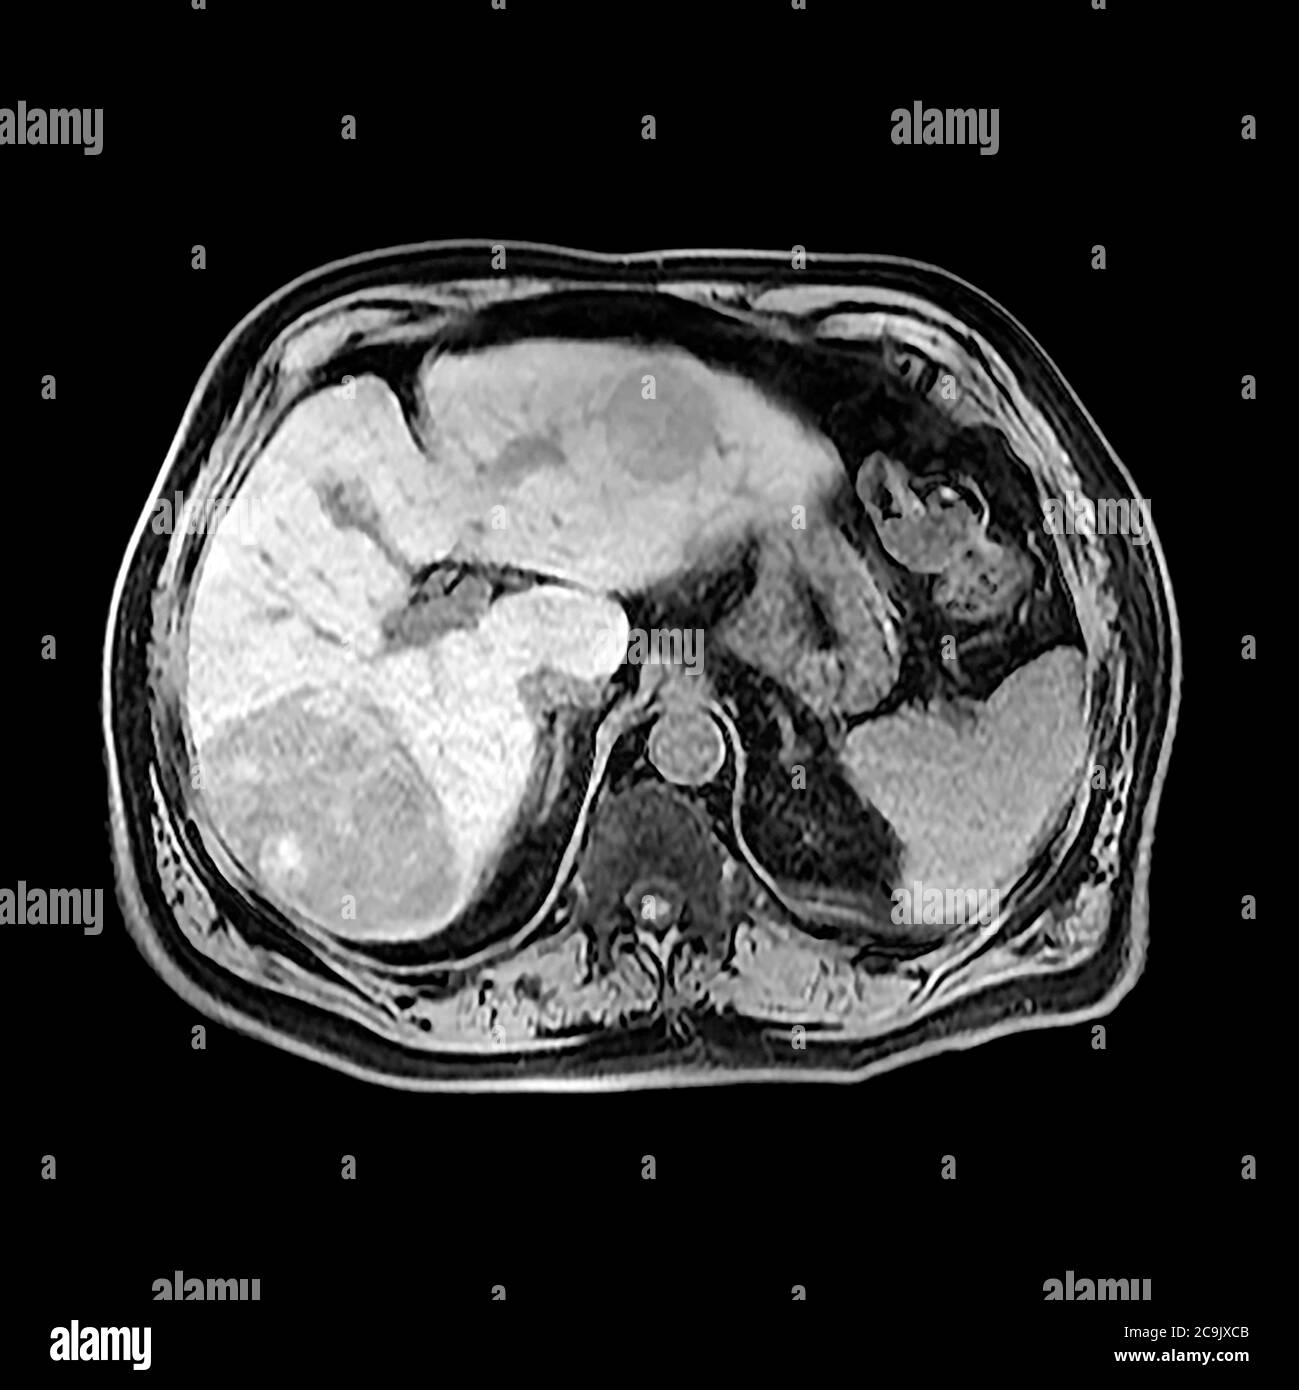

Diagnóstico del cáncer de hígado. Biopsia de hígado Abrir el cuadro de diálogo emergente. Los exámenes y procedimientos utilizados para diagnosticar el cáncer de hígado incluyen los siguientes: Análisis de sangre. Los análisis de sangre pueden revelar anomalías en la función hepática. Pruebas por imágenes.. Las técnicas que se usan para diagnosticar el cáncer de conductos biliares incluyen la ecografía, la tomografía computarizada y la resonancia magnética combinadas con la colangiopancreatografía por resonancia magnética. La colangiopancreatografía por resonancia magnética se usa cada vez más como una alternativa no invasiva a la.